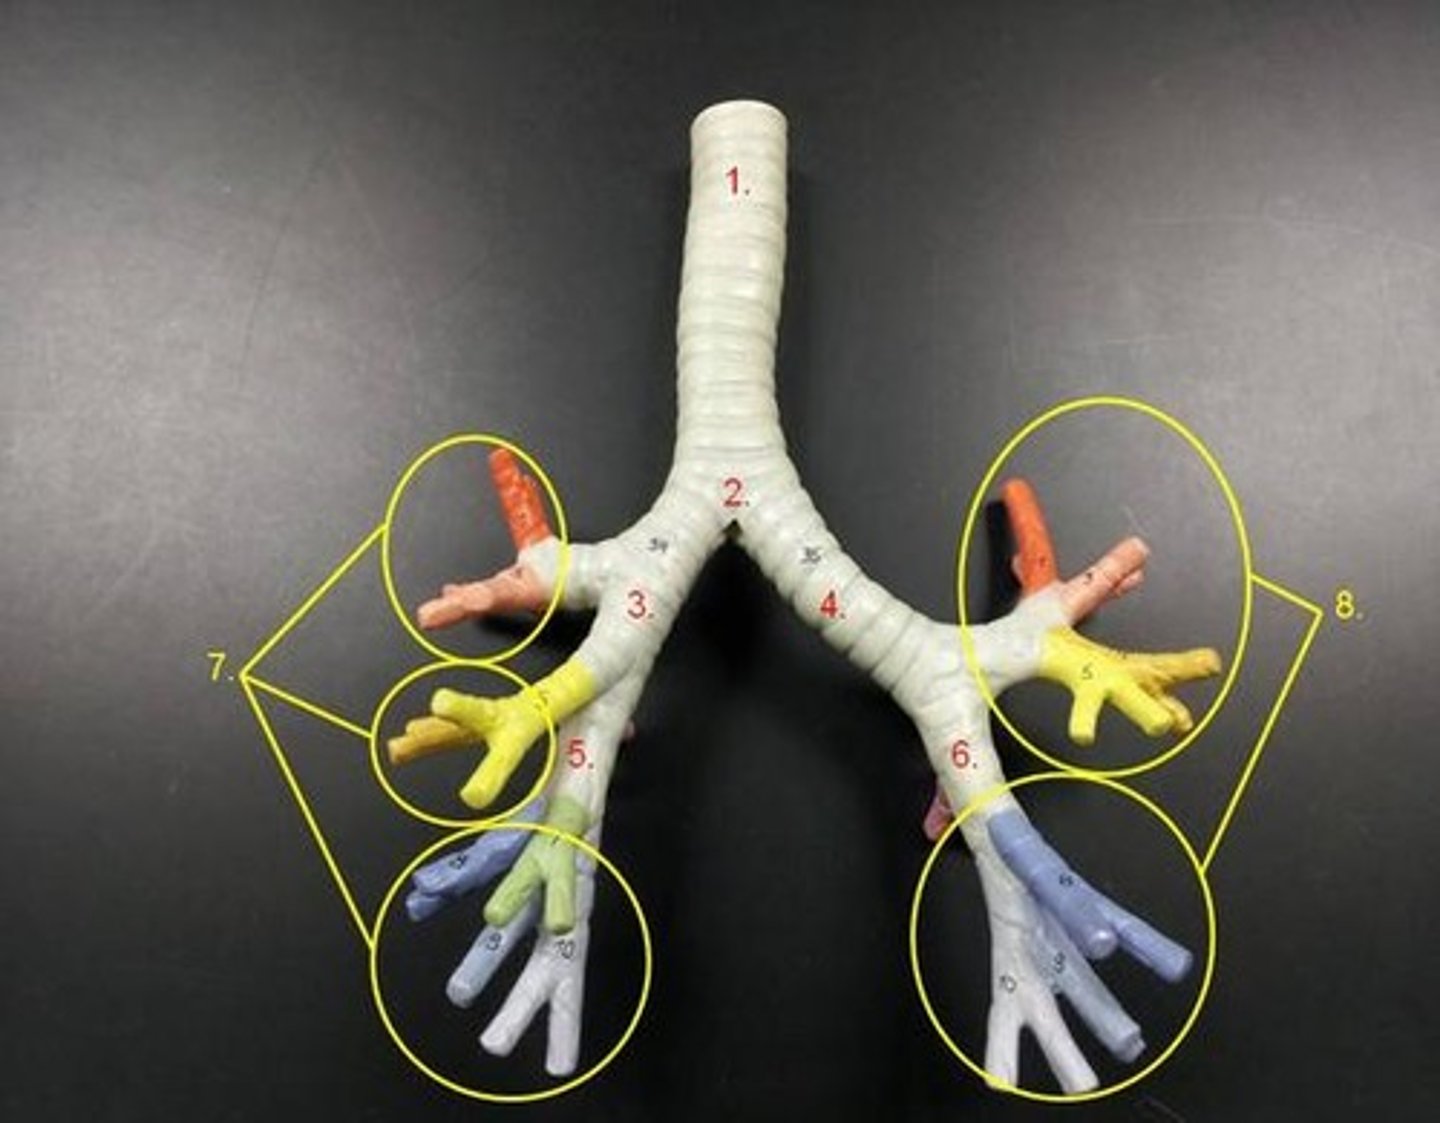

trachea

tube composed of cartilaginous rings and supporting tissue that connects the lung bronchi and the larynx; provides a route for air to enter and exit the lung

tracheal cartilage

C shaped rings of cartilage that give support to the trachea

primary bronchus

The first branches of the trachea. There are two primary bronchi, one for each lung.

secondary (lobar) bronchus

The primary bronchi split into these smaller tubes within the lungs

tertiary (segmental) bronchus

branches of the secondary bronchi that divide into bronchioles; also called segmental bronchi

bronchial tree

collective name for the multiple branches of the bronchi and bronchioles of the respiratory system

bronchiole

branch of bronchi that are 1 mm or less in diameter and terminate at alveolar sacs